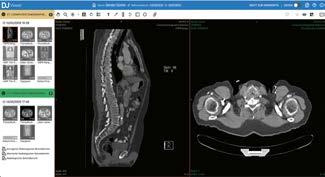

Grenzen entfernen, Wege eröffnen

Michaela Schreiter und Marcus Muth organisieren als Produkt­Manager den Roll­ out der DeepUnity Suite. Die neue Software ­ Suite soll die Radiologie IT enger an die Krankenhaus IT bringen, um die Digitalisierung im Krankenhaus voranzutreiben. Die Bereiche wachsen seit Jahren enger zusammen. Denn Bilder in der Patientenbehandlung, traditionell der Radiologie zugeordnet, entstehen seit längerer Zeit auch in anderen Bereichen. Diese Daten zu vereinheitlichen und klinikweit, sogar über die Grenzen der Klinik hinweg, für Anwender bereitzustellen, ist die Aufgabe von DeepUnity.

DeepUnity besteht aus spezialisierten Lösungen, die – fortschrittlich und modern – schon seit Jahren bei unseren Kunden erfolgreich im Einsatz sind und neuen Applikationen wie dem DeepUnity Viewer, die den Gesamtumfang erheblich erweitern und zukünftig die Bildorganisation unternehmensweit ermöglichen. Mit dem Universalviewer wird der Anwender über eine einzige webbasierte Lösung auf alle Bilddaten und Dokumente zugreifen, seien es nun Röntgenaufnahmen, Bilder einer Wunddokumentation oder andere Medien –unter einer einheitlichen Oberfläche, ohne Medienbrüche, mit einheitlicher Bedienung.

M. Schreiter: Schauen wir auf die aktuelle Situation der Datenhaltung, so liegen zum Beispiel radiologische Daten im PACS, Wunddokumentationen im Bildarchiv und Endoskopieaufnahmen werden in separaten Systemen, unter Umständen gar nicht in der Klinik selbst, gespeichert. Beteiligte Bereiche arbeiten häufig mit eigenen Applikationen und die Daten sind in verschiedenen IT-Systemen abgelegt.

Genau an dieser Stelle setzen wir an. Denn wenn wir die Patienten ganzheitlich behandeln wollen, muss auch die Software genau diese Ganzheitlichkeit liefern. Und dies erreichen wir über DeepUnity, eine Lösung, die Workflows über Grenzen hinweg möglich macht. Dabei übernimmt der sogenannte DeepUnity

Viewer eine zentrale Rolle. Er bietet einheitlichen Zugriff auf DICOM-Bilder, Befunde, Arztbriefe, Wunddokumentationen und Videos – webbasiert und unabhängig von ihrem Ursprung.